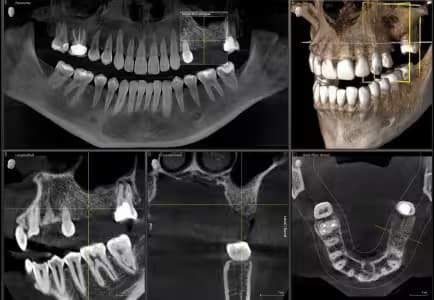

Advanced diagnostic technologies